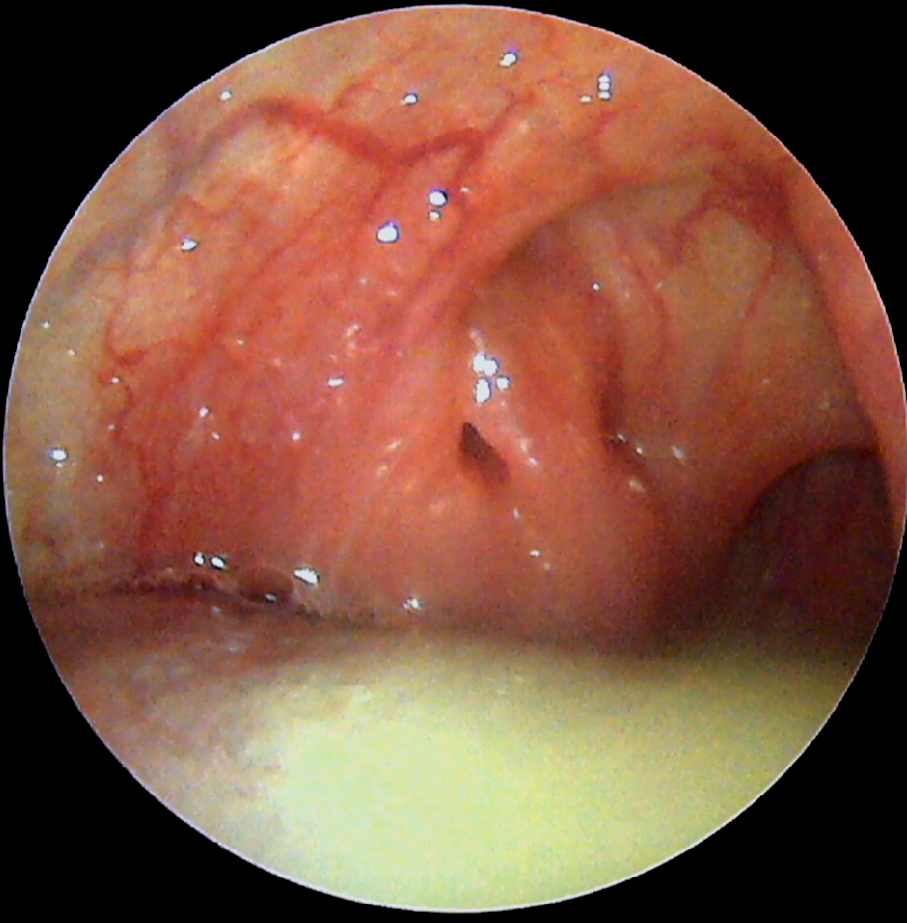

목 한쪽에 치우친 이물감을 호소하면서 점점 심해지는 것 같다고 말하는 환자의 이물감은 편도결석 때문인 경우가 많습니다 그 외에 물고기의 가시나 편도에 생긴 종양이 원인이었던 환자도 있습니다. 편도선에 악성종양(암)이 생기는 일은 결코 드물지 않으므로 목의 이물감을 자가진단만으로 가볍게 끝내서는 안 됩니다” 특히 노인이나 흡연자일 경우 주의합시다.진단 : 이비인후과 내시경 검사에서 자세히 관찰하여 눈으로 보기만 해도 잘 보이는 편도 결석이 있는 반면 가려 보이지 않는 편도 결석이 있습니다. 그래서 샅샅이 살펴보셔야겠지만 편도선이 있는 입 깊숙한 곳에는 울퉁불퉁한 구조물이 많아 눈과 설압자(혀를 누르는 막대기)만으로 전체 구조물을 다 관찰하는 데는 한계가 있습니다.

A근육과 편도 사이의 공간, 혀에 가려진 아래쪽 편도 B까지 모두 관찰하는데 사용하는 것이 위쪽과 같은 이비인후과 내시경입니다. 이비인후과 의사에게 둘도 없는 무기입니다. 구강 내 가장 깊은 곳의 후두를 관찰할 때 외에도 편도 주변을 꼼꼼히 살펴볼 필요가 있다고 판단되면 이비인후과 내시경을 입 안으로 삽입하여 관찰합니다. 다만, 이비인후과 내시경은 특별한 훈련을 받은 이비인후과 전문의만 실시할 수 있기 때문에 기본 진료비 이외에 몇 천원의 추가 진료비가 발생함을 양해해 주셔야 합니다.(그래도 위 카메라 등에 비하면 매우 저렴합니다.)

치료 : 편도결석 제거를 해보세요 석션으로 빨아내거나 포셉으로 끌어내거나 작은 스푼과 같은 기구로 퍼내거나 날카로운 타액으로 소곤소곤 꺼내거나 합니다. 보이는 것보다 훨씬 깊게 구불구불한 것이 많기 때문에 중간에 잘리지 않게 살며시 달래서 꺼내야지만 완전히 적출이 가능해요. 이 때 약간의 피가 나올 수도 있지만, 대개는 문제 없이 지혈하기 때문에 놀라지 않아도 괜찮습니다.